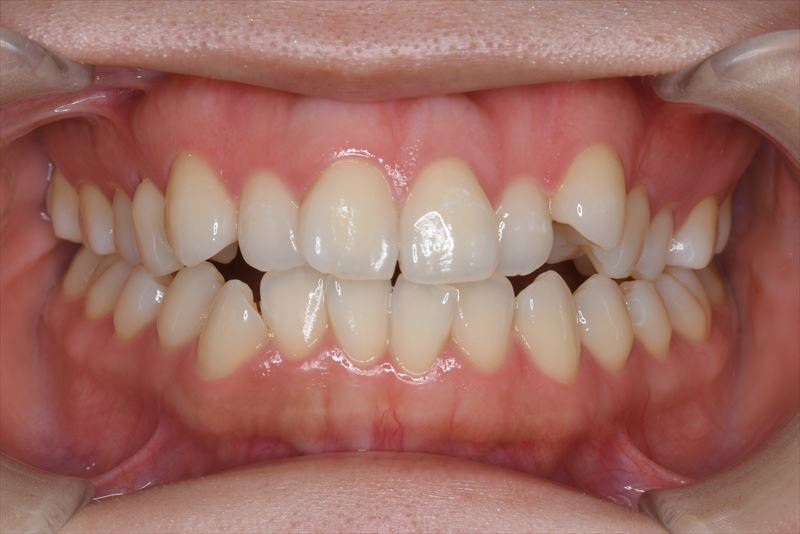

治療前

前歯で咬めない。歯が重なっている。

叢生、口唇の突出